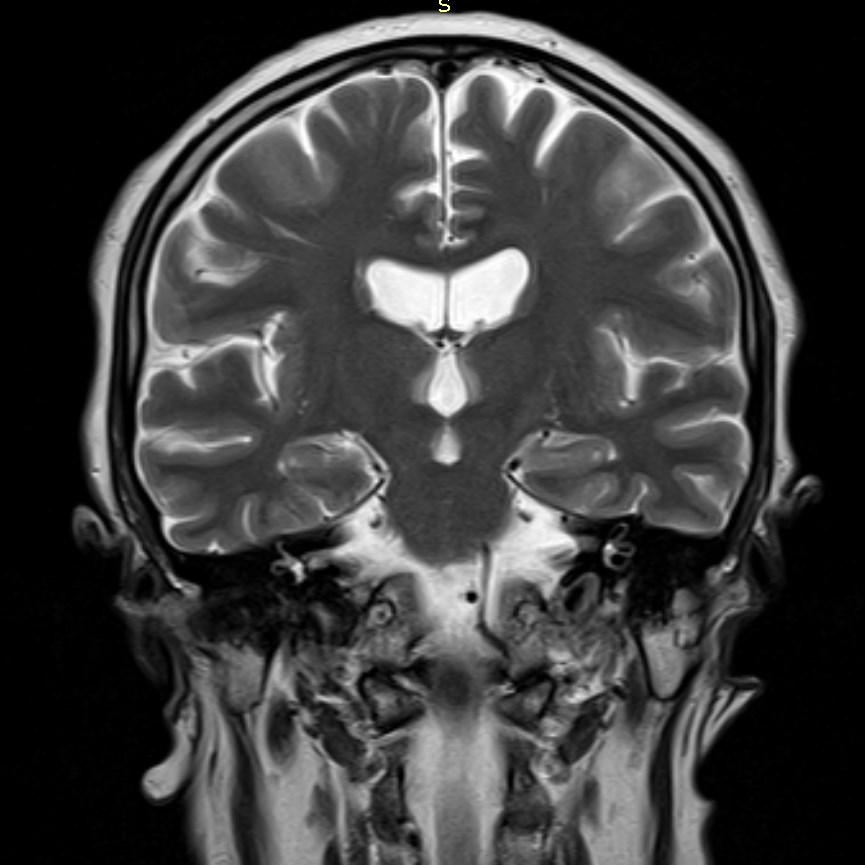

MRI images revealed hyperintensities in the periaqueductal region and the medial thalami.

MRI

T2/FLAIR: symmetrically increased signal intensity in the mamillary bodies, dorsomedial thalami, tectal plate, periaqueductal area, and around the third ventricle.